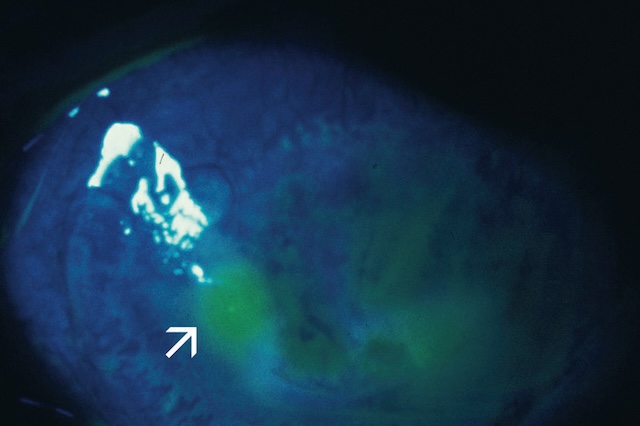

B 34Angiographie du fond d’œil (fig. 1.57)

C’est la prise de clichés du fond d’œil après injection intraveineuse d’un colorant fluorescent qui est, suivant les indications, soit de la fluorescéine, soit du vert d’indocyanine. Examen de réalisation simple, il ne présente que peu d’effets secondaires et de complications et peut être pratiqué chez la femme enceinte. Il existe cependant un risque très faible mais réel de choc anaphylactique.

1 Angiographie fluorescéinique

Après injection de fluorescéine, des clichés photographiques en série à l’aide d’un filtre bleu permettront d’en visualiser le passage dans les vaisseaux rétiniens artériels puis veineux 35(fig. 1.58). L’angiographie fluorescéinique réalise ainsi une étude dynamique de la vascularisa-tion rétinienne.

Sur le premier cliché (A), on observe une vue de fond d’œil capturée lors d’une angiographie fluorescéinique, illustrant la phase initiale du remplissage artériel. Les artères rétiniennes, bien dessinées, laissent apparaître les premiers passages du produit de contraste fluorescent. Le réseau vasculaire se détache progressivement sur un fond sombre, annonçant la dynamique circulatoire. Sur le second cliché (B), la phase veineuse de cette même angiographie est mise en évidence. Les veines rétiniennes, désormais bien remplies, tracent un motif plus large et contrasté que celui des artères. L’ensemble forme un schéma complet de la perfusion rétinienne, permettant d’examiner finement la continuité des vaisseaux et d’éventuelles anomalies. Ce type de photographie est utilisé dans les bilans visuels pour analyser les troubles vasculaires de la rétine sans recourir à une reconstruction numérique ou magnétique.